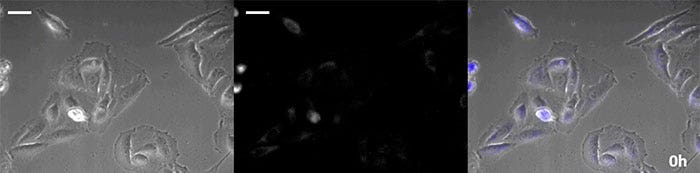

Brightfield image

Luminescence image

Overlay image

Luminescence image pseudo color (green)

Video 1. Luminescence observation of calcium ion fluctuations caused by histamine stimulation (scale bar: 500 µm)

0 hours